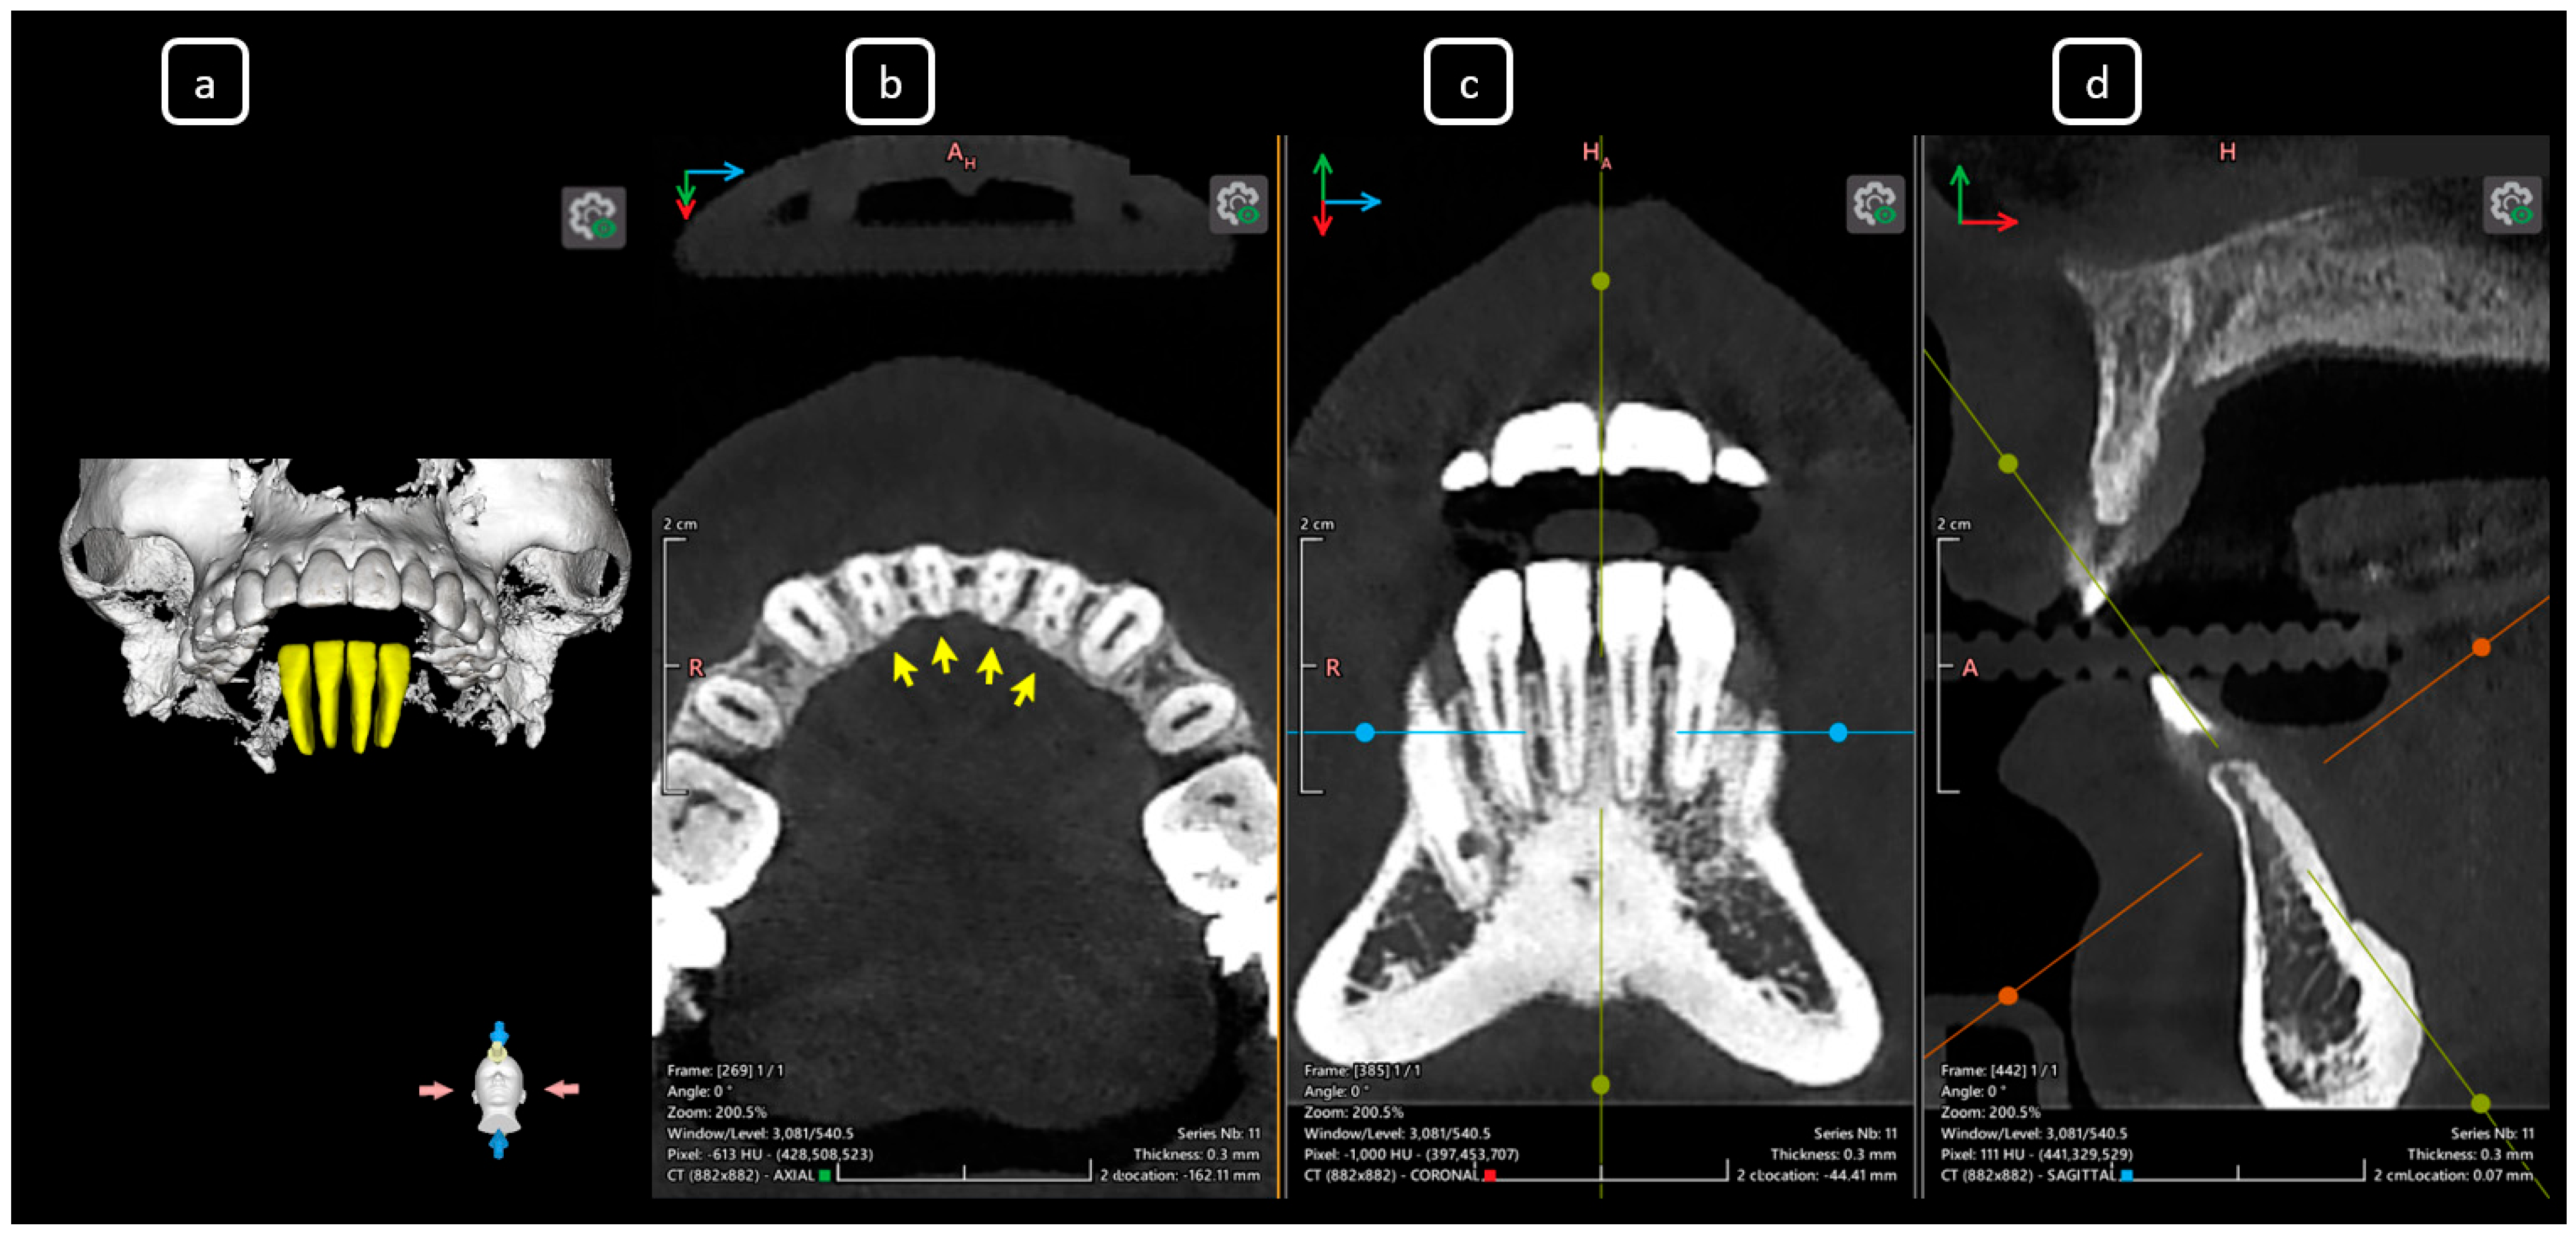

Imaging Findings of Clinical Significance in Endodontics During Cone Beam Computed Tomography Scanning of the Upper Airway—The Anterior, Bilateral, C-Shaped, Dual of Mandibular Root Canals: A Brief Case Report

García-Torres, E.; Guerrero-Falcón, D.L.G.; Bojórquez-Armenta, H.A.; Almeda-Ojeda, O.E.; Barajas-Pérez, V.H.; Solís-Martínez, L.J. Imaging Findings of Clinical Significance in Endodontics During Cone Beam Computed Tomography Scanning of the Upper Airway—The Anterior, Bilateral, C-Shaped, Dual of Mandibular Root Canals: A Brief Case Report. Diagnostics 2025, 15, 3157. https://doi.org/10.3390/diagnostics15243157